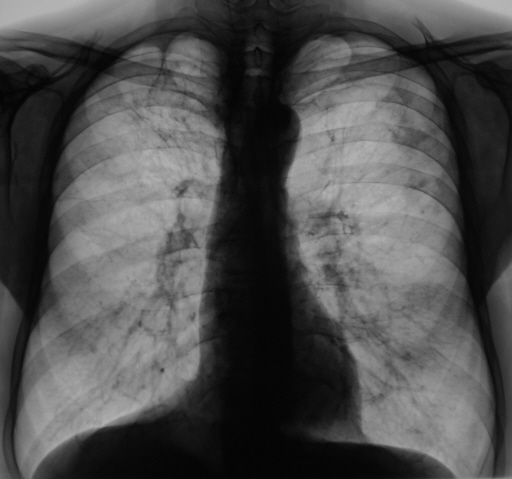

4 месяца тому пациент "взят на контроль". Произведено дообследование пациента - рентгенография, линейная томография в прямой проекции. Был заподозрен инфильтративный туберкулёз левого лёгкого в фазе распада. Пациент был направлен в противотуберкулёзный диспансер, диагноз был подтвержден. Было проведено "специфическое лечение".

Пациент направлен на рентгенологические исследование с целью динамики.